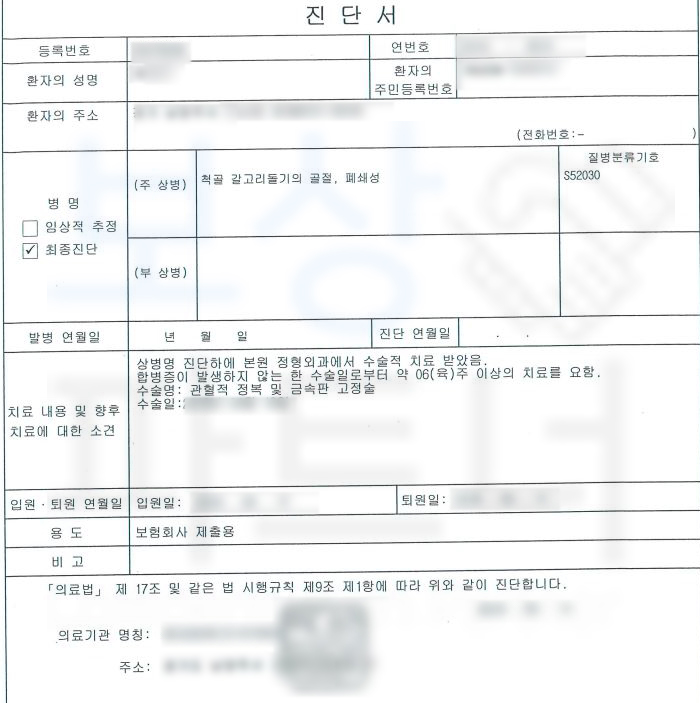

진단서를 보시면

척골 갈고리돌기 의 골절 S52030 팔꿈치골절 진단을 받으셨고 금속 고정술을 시행하셨습니다.

문제는 수술 후 재활치료를 진행하셨음에도 팔꿈치 관절의 통증과 움직임에 어려움을 호소하셨고 유@@님은 자신과 같은 상황에 골절진단비를 제외한 장해 보상을 받은 보상파트너의 사례를 보고 연락주셨습니다.

보상파트너는 유@@님의 보험증권과 진단서, 의무기록을 받아 분석하였고 유@@님의 현재 상황과 비교했을 때 장해 보상 가능성 확신하였습니다.

보상파트너는 유@@님의 장해약관에 근거한 올바르고 객관적인 장해평가를 위해 공신력있는 대학병원의 전문의로부터 후유장해 평가를 의뢰했고 그 결과,

주관절의 뚜렷한 기능장해 10% 6급에 해당하였습니다. 물론 위 진단서를 기초로 각 보험사에 청구하였지만 조사관이 배정되어 내부 의료자문도 해야했습니다. 하지만 보상파트너는